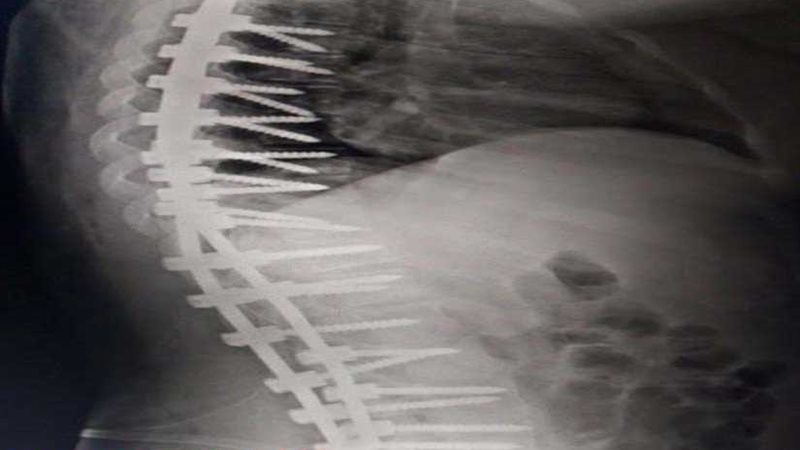

نجح فريق طبي بمستشفى الملك عبد الله بن عبد العزيز بمحافظة "بيشة" السعودية في إنهاء معاناة فتاة من تحدب وانحناء العمود الفقري.

وقالت وكالة الأنباء السعودية "واس": إن الفريق الطبي المعالج للفتاة قرر- بعد إجراء الفحوصات الطبية- خضوع المريضة لعملية جراحية جرى خلالها تعديل الفقرات الصدرية والقطنية وتثبيتها، تكللت العملية بالنجاح وتحسنت الحالة الصحية للمريضة، بعد شفائها من التحدب والانحناء.